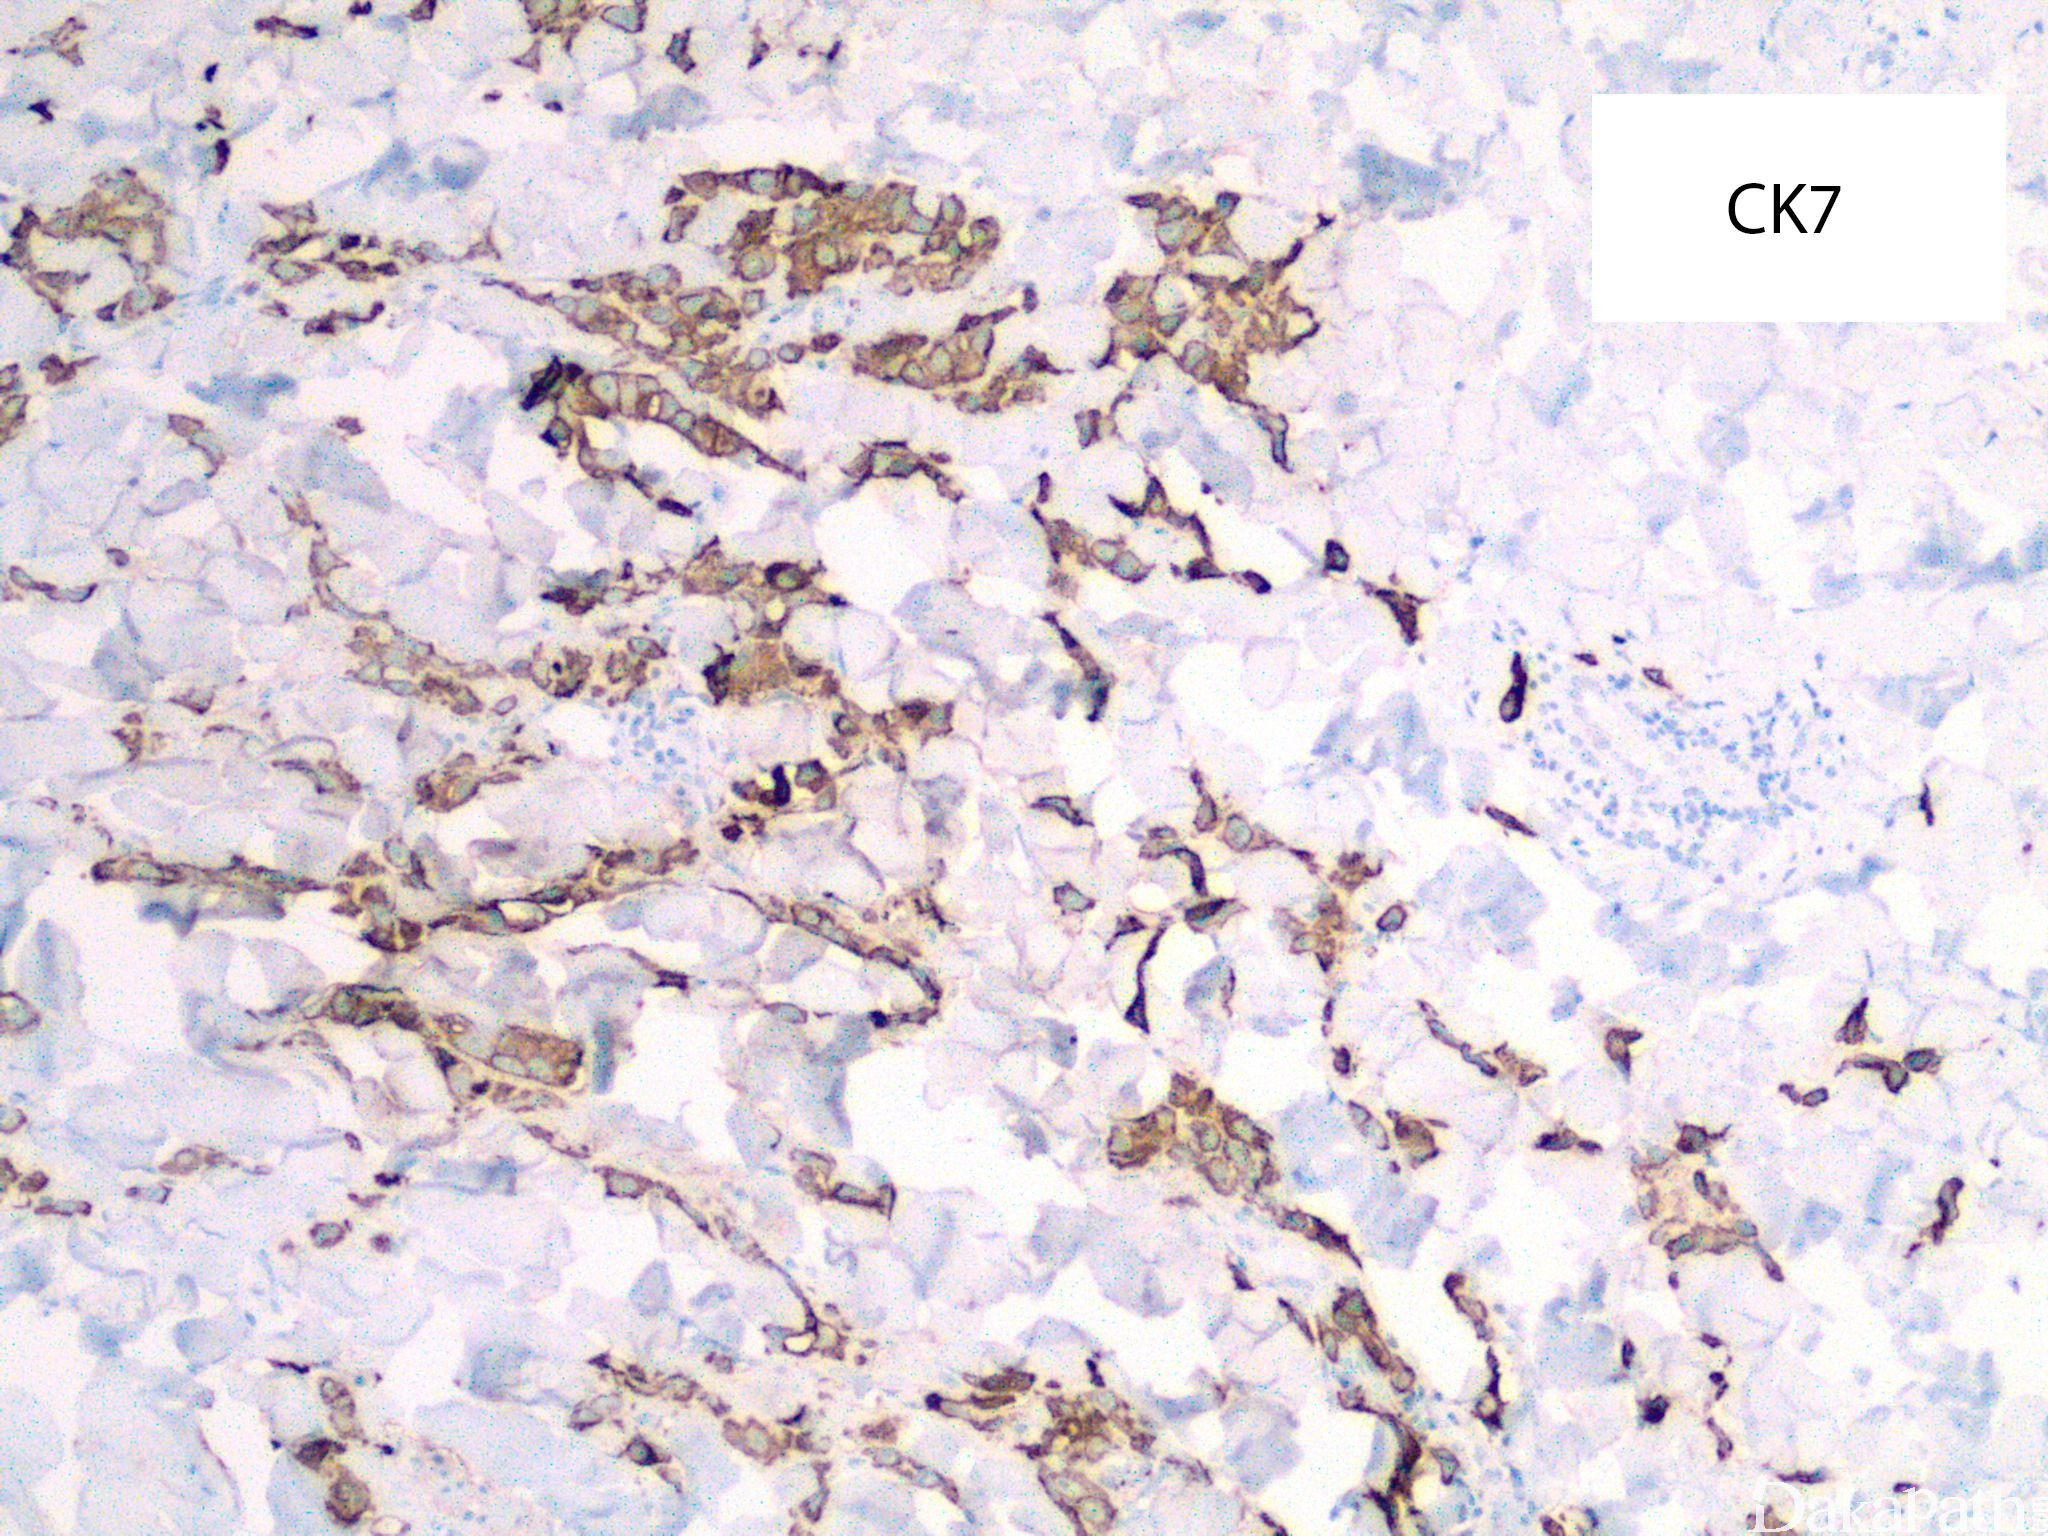

皮肤乳腺转移癌